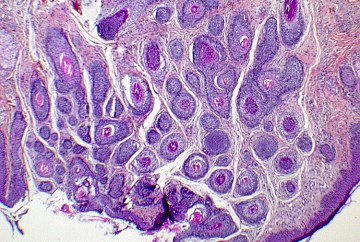

Les médecins spécialistes du Centre de Pathologie Émile Gallé Groupe interviennent sur tous les champs de la pathologie. Ils réalisent un diagnostic de lésions et maladies dont principalement le cancer, à partir de l’analyse des tissus et des cellules sur des prélèvements réalisés par d’autres médecins spécialistes.

Intégrés dans une équipe pluridisciplinaire, les médecins pathologistes sont un maillon de la chaîne de soins. Leur diagnostic retranscrit sous la forme d’un compte-rendu déclenche la prise en charge thérapeutique.

Diagnostic médical au microscope